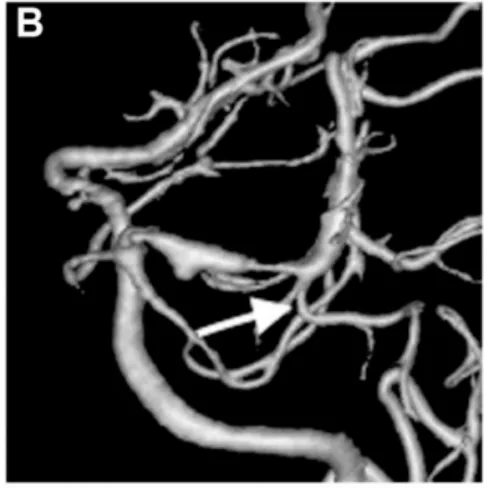

出血后第18天,待陳先生狀況穩(wěn)定后,醫(yī)生進(jìn)行了腦血管造影檢查(圖B)。結(jié)果顯示,左側(cè)大腦后動脈P1-P2段出現(xiàn)異常擴(kuò)張伴狹窄——這是夾層動脈瘤的特征表現(xiàn)。

出血后18天血管造影顯示左側(cè)P1-P2段擴(kuò)張伴狹窄特征,顳后動脈自狹窄病變遠(yuǎn)端發(fā)出(箭頭標(biāo)注)